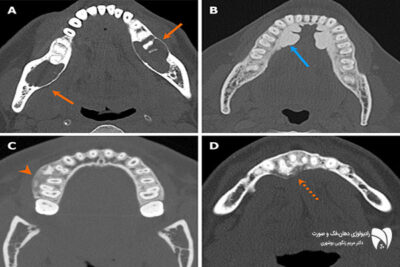

دقت CBCT در مقایسه با روش‌های سنتی تصویربرداری فک را بررسی کنید. تصویربرداری پیشرفته فک چگونه به تشخیص دقیق فک کمک می‌کند؟

مقایسه دقت تصویربرداری CBCT با روش‌های سنتی در تشخیص بیماری‌های فک

دقت CBCT یکی از مهم‌ترین معیارها در بررسی روش‌های تصویربرداری پیشرفته فک است. در این مطلب،...

CBCT یا رادیوگرافی سنتی؟ تفاوت‌ها، مزایا و کاربردهای هر روش را بررسی کنید و بهترین گزینه را برای تصویربرداری دندان و فک خود انتخاب کنید.

تفاوت CBCT با رادیوگرافی معمولی: کدام بهتر است؟

CBCT در مقایسه با رادیوگرافی معمولی یکی از پیشرفته‌ترین روش‌های تصویربرداری در دندانپزشکی ...